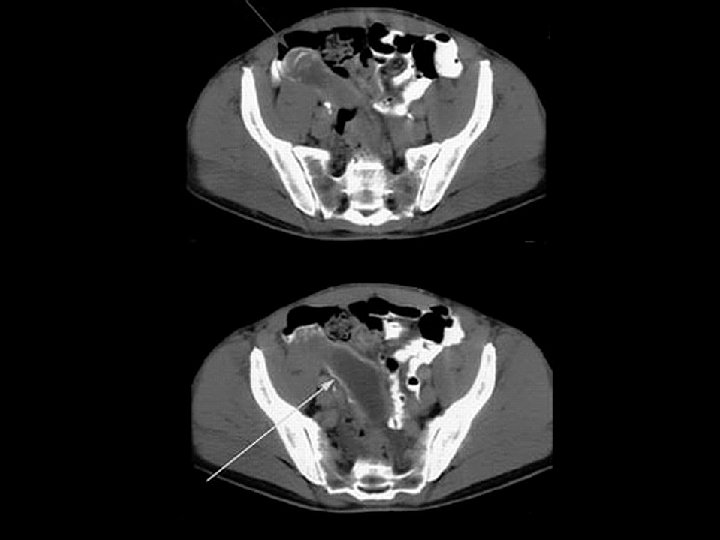

Ovarian cystadenocarcinoma • Findings: – Large multilocular cystic lesion with fine septa in the right hemipelvis • ddx: – Ovarian cystadenoma – Tubo-ovarian abscess – Mucocele of the appendix